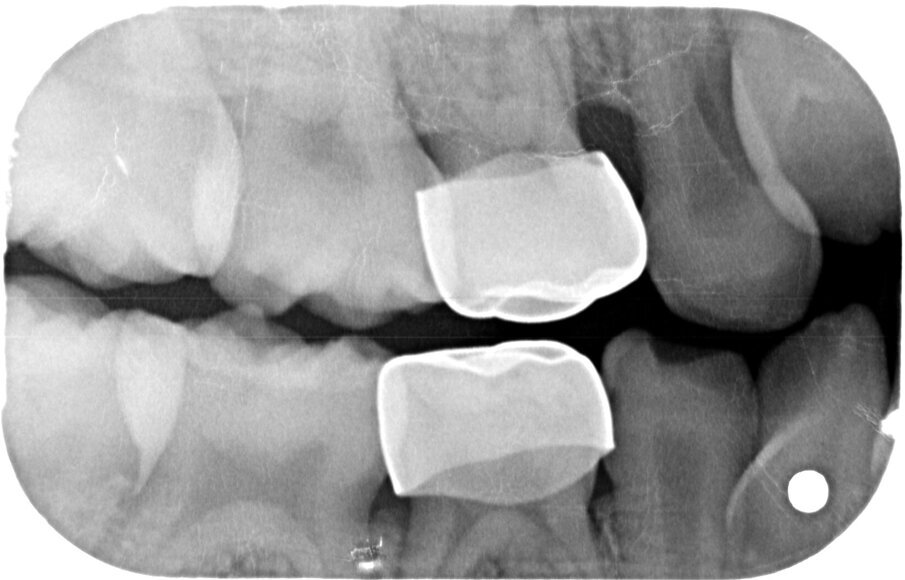

Afbeelding 9. Casus 3: 18-10-19. BWR, zie 55.

Afbeelding 10. Casus 3: 18-10-19. BWL, zie 65.

Groot voordeel van de Hall-techniek is dat deze eigenlijk altijd eenmalig is. De kans op herbehandeling vanwege loslaten, breuk, secundaire cariës of wat dan ook is lager dan bij elke andere therapie. De diepte of de grootte van de caviteit is van secundair belang. De prognose van de therapie wordt bepaald door de afwezigheid van pulpa-pathologie en door de aanwezigheid van een op een bitewing zichtbare laag van gezond dentine, ‘a clear band of dentine’, tussen de caviteit en de pulpa (afbeelding 12-13).